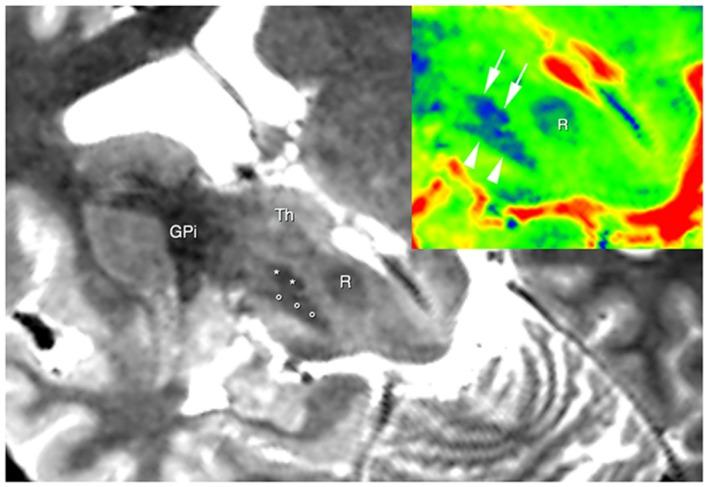

The connections between the cerebellum and basal ganglia were assumed to occur at the level of neocortex. However evidences from animal data have challenged this old perspective showing extensive subcortical pathways linking the cerebellum with the basal ganglia. Here we tested the hypothesis if these connections also exist between the cerebellum and basal ganglia in the human brain by using diffusion magnetic resonance imaging and tractography. Fifteen healthy subjects were analyzed by using constrained spherical deconvolution technique obtained with a 3T magnetic resonance imaging scanner. We found extensive connections running between the subthalamic nucleus and cerebellar cortex and, as novel result, we demonstrated a direct route linking the dentate nucleus to the internal globus pallidus as well as to the substantia nigra. These findings may open a new scenario on the interpretation of basal ganglia disorders.

小脑与基底神经节之间的连接曾被认为发生在新皮层水平。然而,动物数据的证据对这一旧观点提出了挑战,显示出连接小脑与基底神经节的广泛皮质下通路。在这里,我们通过使用扩散磁共振成像和纤维束成像技术,测试了人类大脑中小脑与基底神经节之间是否也存在这些连接的假设。对15名健康受试者使用3T磁共振成像扫描仪获得的约束球形反卷积技术进行分析。我们发现丘脑底核与小脑皮质之间存在广泛连接,并且作为新的结果,我们证明了一条将齿状核与苍白球内部以及黑质相连的直接路径。这些发现可能为基底神经节疾病的解释开辟一个新的局面。